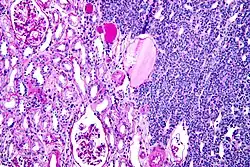

Micrograph of a metanephric adenoma (right of image). Normal kidney is seen on the left. Kidney biopsy. PAS stain.

Micrograph of a metanephric adenoma, right of image, showing the characteristic features (round nuclear membrane, no nucleoli, and fine chromatin). Normal kidney is seen on the left of the image. Kidney biopsy. PAS stain.

Metanephric adenoma is diagnosed histologically. The tumours can be located at upper pole, lower pole and mid-hilar region of the kidney; they are well circumscribed but unencapsulated, tan pink, with possible cystic and hemorrhagic foci. They show a uniform architecture of closely packed acinar or tubular structures of mature and bland appearance with scanty interposed stroma.[3][4][5][6][7] Cells are small with dark staining nuclei and inconspicuous nucleoli. Blastema is absent whereas calcospherites may be present. Glomeruloid figures are a striking finding, reminiscent of early fetal metenephric tissue. The lumen of the acini may contain otherwise epithelial infoldings or fibrillary material but it is quite often empty. Mitoses are conspicuously absent.[3][4][5][6][7] In the series reported by Jones et al. tumour cells were reactive for Leu7 in 3 cases of 5, to vimentine in 4 of 6, to cytocheratin in 2 of 6, to epithelial membrane antigen in 1 of 6 cases and muscle specific antigen in 1 of 6.[5] Olgac et al. found that intense and diffuse immunoreactivity for alpha-methylacyl-CoA racemase (AMACR) is useful in differentiating renal cell carcinoma from MA but a panel including AMACR, CK7 and CD57 is better in this differential diagnosis.[8] Differential diagnosis may be quite difficult indeed as exemplified by the three malignancies initially diagnosed as MA that later metastasized, in the report by Pins et al.[9]